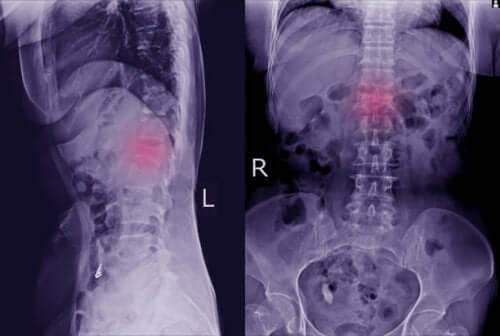

Essas manifestações físicas podem ser negligenciadas. No entanto, prestar atenção nelas nos permitirá ir ao médico para realizar um dos principais exames que permitirão a sua detecção: o raio-x. Assim, será possível ver claramente se há alguma vértebra deslocada.

Em alguns casos, o médico pode exigir testes mais específicos, como topografia computadorizada e ressonância magnética. Com esses testes adicionais, é possível observar com mais clareza se há espondilolistese, e também se ela afetou ossos e nervos.